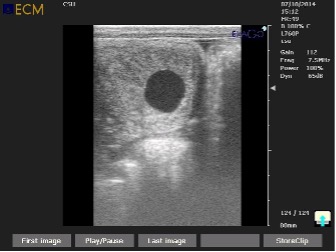

Pre-breeding checks are routine ultrasound scans of the uterus, ovaries, and other examinations to determine the optimal time to breed. This evaluation normally includes ultrasound scans, vaginal evaluation, and all the follow-ups in order to ensure the most accuracy of breeding. Each mare is treated to suit her needs and/or difficulties according to each animal's individuality.

The recipient mare will be checked between 12 to 14 days (embryo age) to determine confirmation. Follow-up will be done at 30 days of pregnancy to ensure the embryo has a heartbeat and viability confirmation. Follow-ups on these mares are necessary every couple of weeks until 2 months, which is the critical period.

• Ultrasound examination